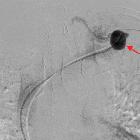

Subclavian

vein aneurysm - Case presentation and discussion. Venography of the left subclavian vein after catheterization and subsequently of the aneurysm, shows filling of the venous dilatation after the injection of contrast media, with preserved patency of the subclavian vein.

vein aneurysm - Case presentation and discussion. Venography of the left subclavian vein after catheterization and subsequently of the aneurysm, shows filling of the venous dilatation after the injection of contrast media. The dimensions of the lesion are noted.